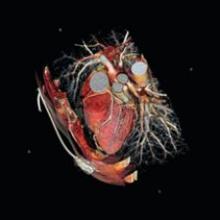

August 31, 2007 - TomTec Imaging Systems recently announced that a new version of the 4D RV-Function software, with a new routine oriented clinical workflow, will be launched at the European Society of Cardiology congress 2007, in Vienna.

The software reportedly allows the physician to completely analyze the right ventricle by referring to familiar anatomical structures. This may be accomplished without any experiences in 3D echocardiography.

For more information: www.tomtec.de